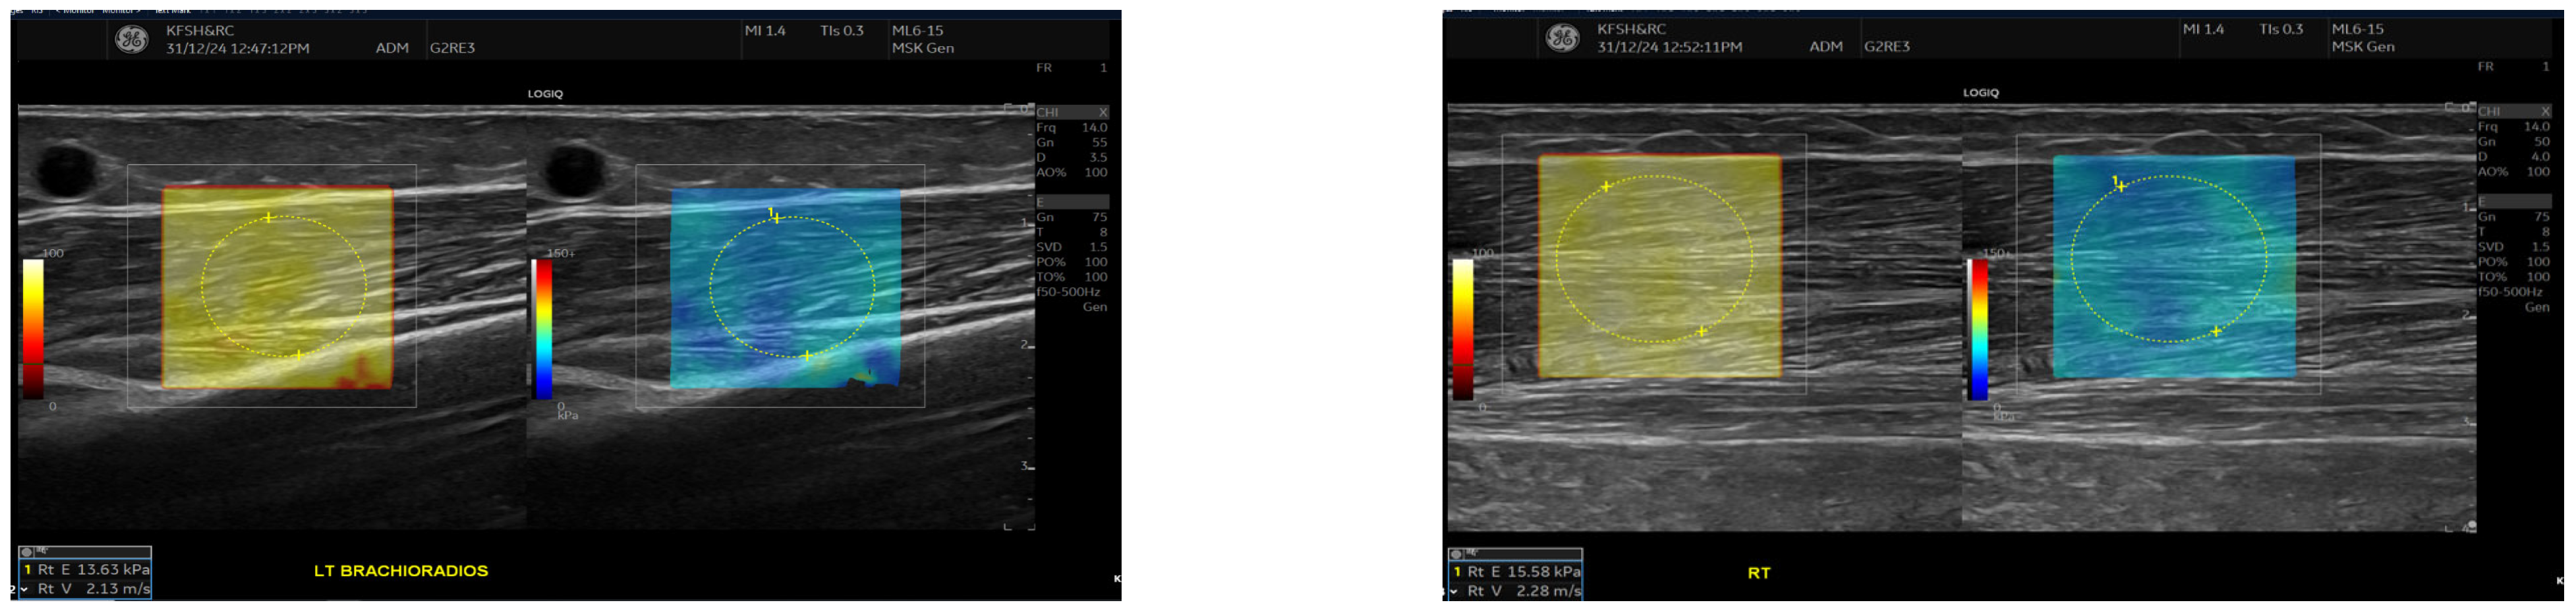

SWE measurements were acquired using a GE LOGIQ E10 (GE HealthCare, Chicago, IL, USA) system equipped with an ML 6-15 D linear transducer (frequency 6–15 MHz). Depth settings were standardized at 2.5–3.5 cm depending on muscle thickness. Each ROI was circular with a 5–7 mm diameter, placed centrally within the elastograms, avoiding fascia, vascular structures, and visible artefacts. Stiffness values were recorded in both kilopascals and metres/second, although statistical analyses were conducted using shear-wave velocity (m/s) for consistency. Frames with motion or colour dropout were discarded and reacquired. Muscle stiffness and thickness were evaluated in the biceps brachii and brachioradialis muscles, located proximal to the AVF site, Figure 1 and Figure 2. SWE imaging provided both Colour-coded elastograms and quantitative stiffness measurements (m/s; Figure 3). Participants were examined supine, with the shoulder in neutral rotation, the elbow extended to approximately 10–20°, and the forearm supinated. This minimized passive tension, which can influence shear-wave velocity. The transducer was positioned perpendicular to the muscle fibres, capturing measurements from the proximal, middle, and distal regions for comprehensive analysis. Measurements were taken before the haemodialysis to avoid intravascular volume shifts, with each parameter recorded three times and averaged for precision. Scans were performed by an experienced sonographer and verified by a radiologist, minimizing bias. A preliminary review of some patient records was conducted to refine data collection tools before the main data collection.

Figure 1.

This figure shows the Ultrasound assessment of stiffness near the arteriovenous fistula site (A) and brachioradialis muscle thickness (B). Shear wave elastography images (A) obtained at the fistula side demonstrate quantitative stiffness mapping within a defined region of interest, with stiffness expressed in velocity in metres per second (m/s). B-mode image (B) showing brachioradialis muscle thickness measurement at the contralateral (right) arm.

Figure 2.

This figure demonstrates the comparison of brachioradialis muscle thickness between the fistula (A) and the contralateral arm (B). B-mode ultrasound images showing brachioradialis muscle thickness measurements. The left panel (A) (fistula side) demonstrates reduced muscle thickness (1.14 cm) compared with the contralateral arm (right panel (B), 1.74 cm). Measurements were obtained in the mid-muscle belly using a linear high-frequency transducer.